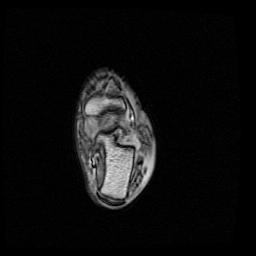

庆幸骨头没事,单肌腱拉伤,静养中